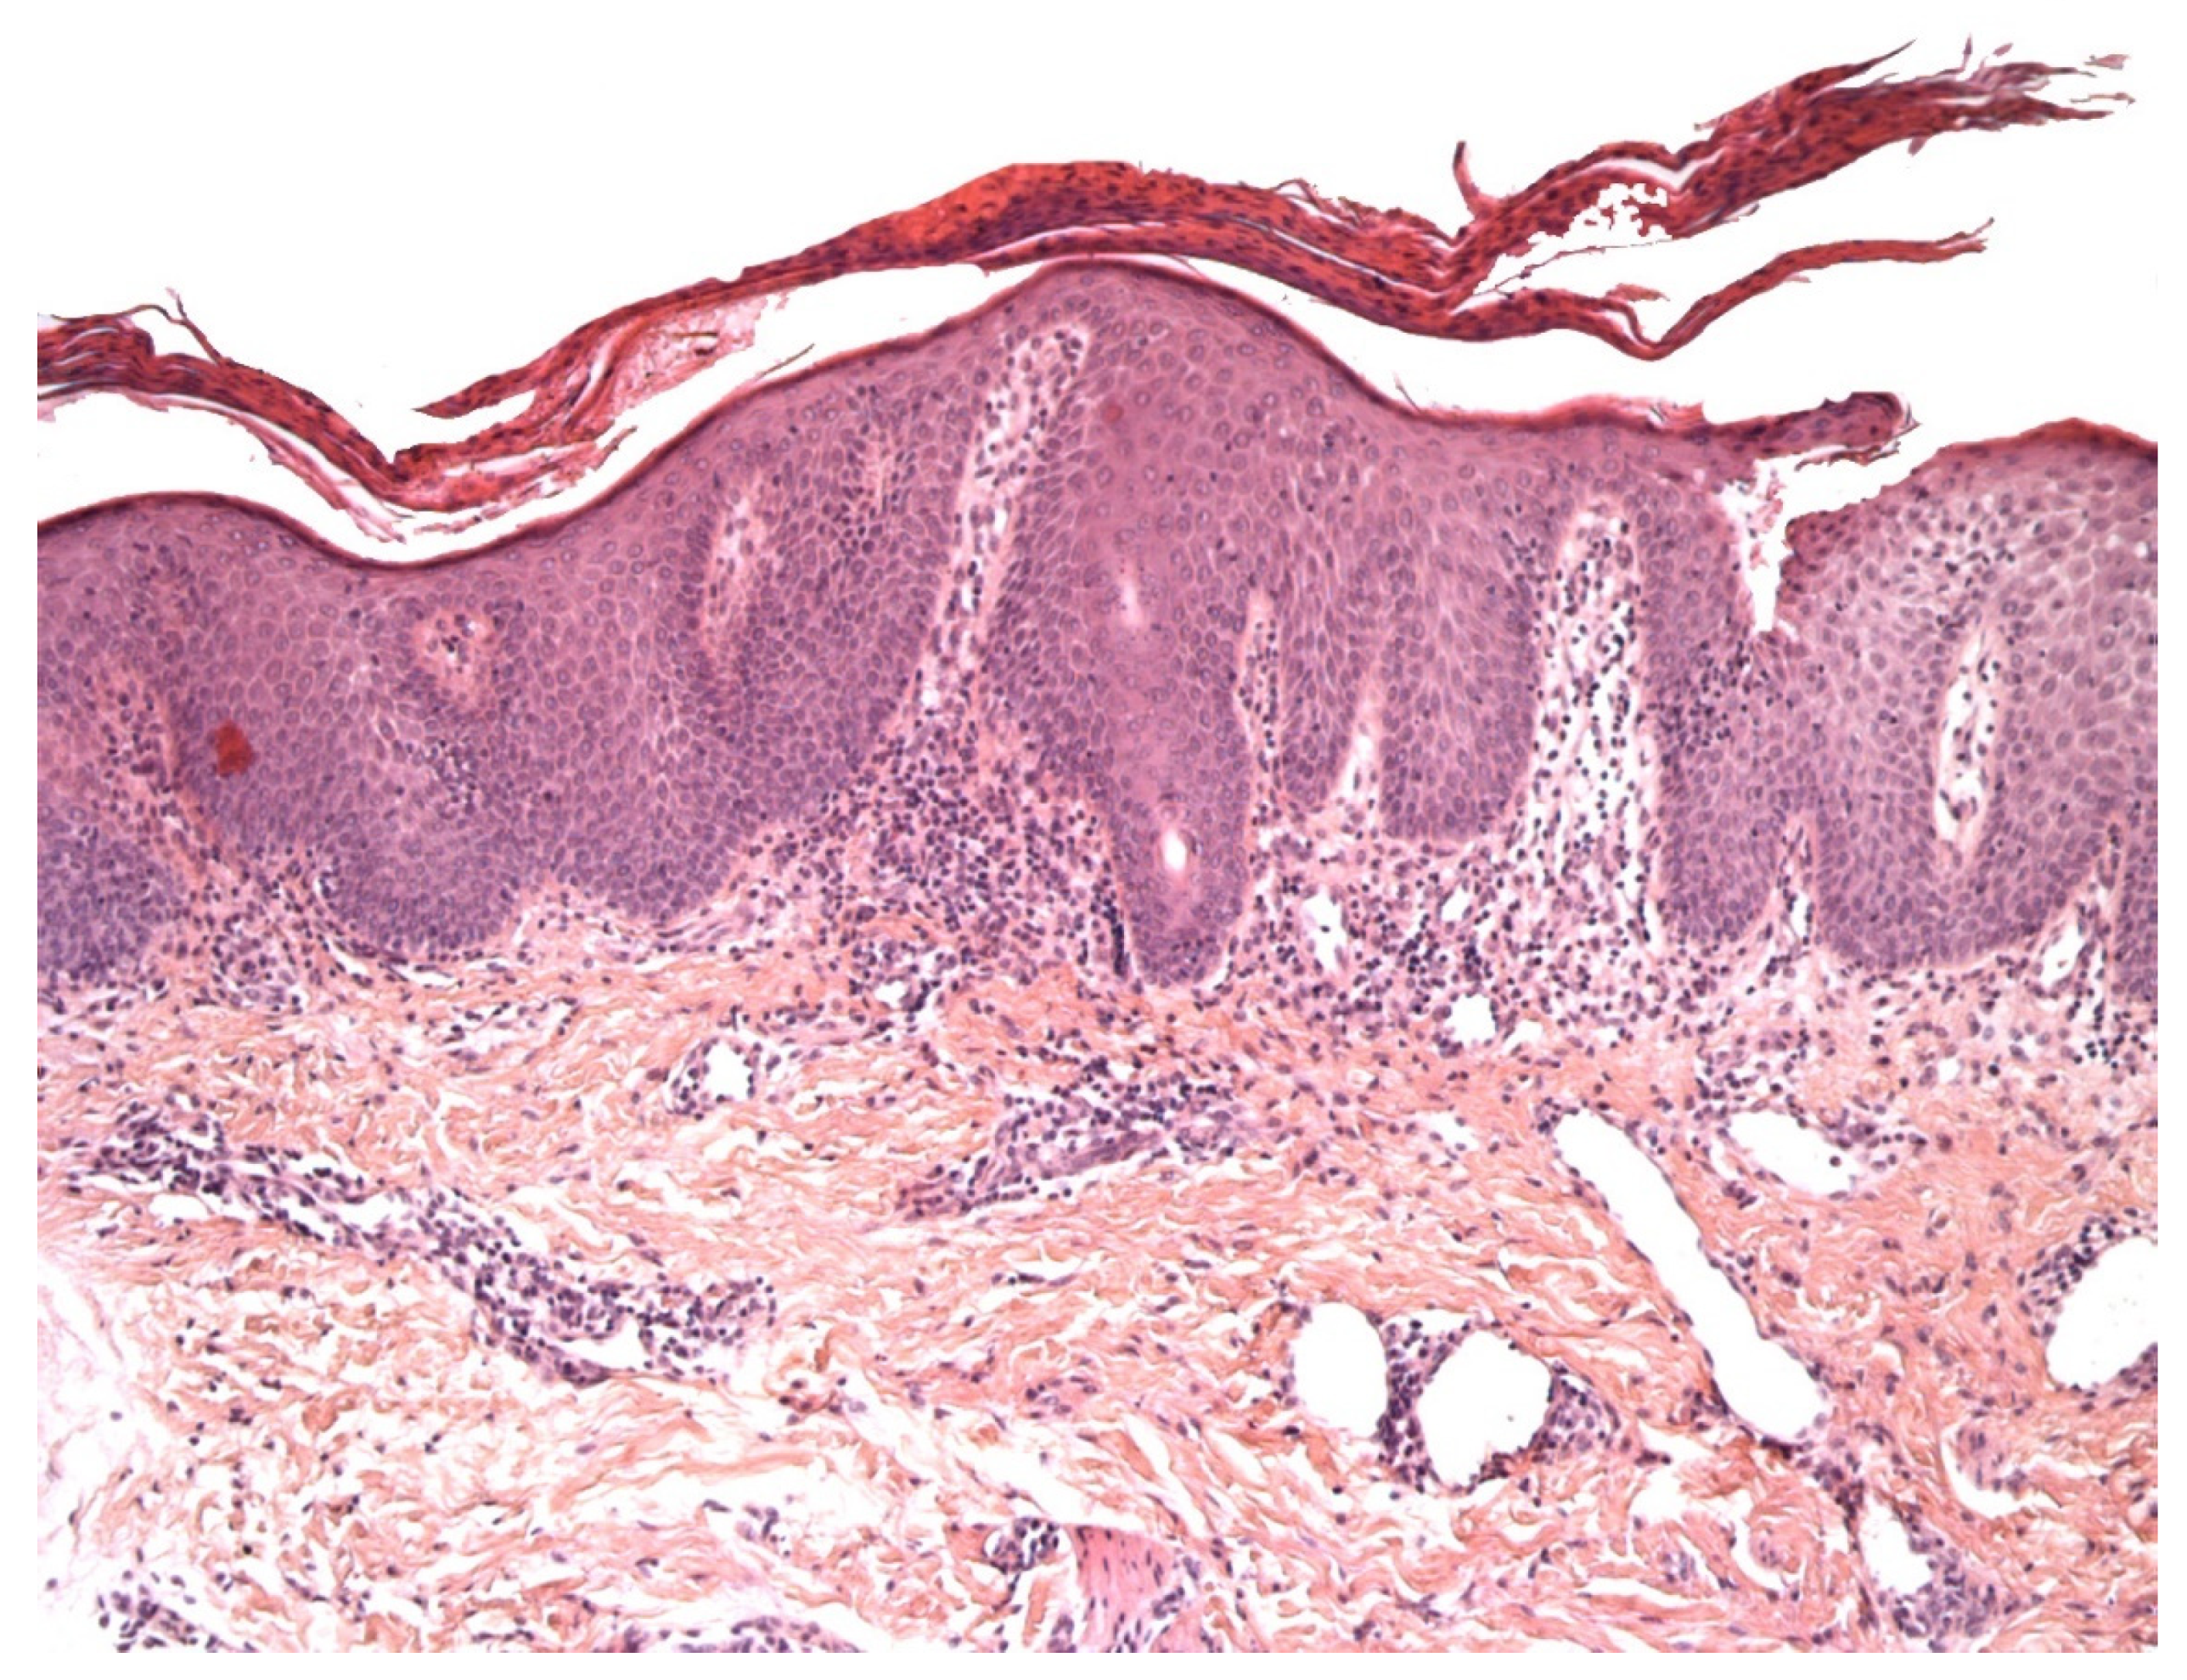

2.1. Vitiligo